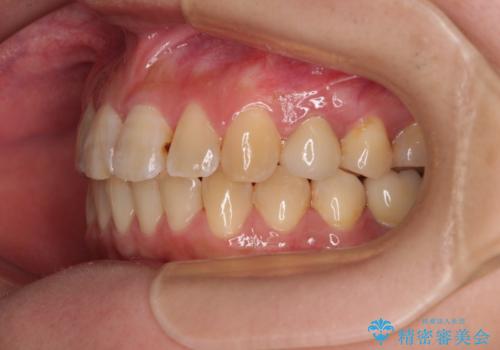

- 奥歯に問題が多くて困っているとのことで来院された患者様です。

開咬により奥歯のみが接触している状態で、前歯部にほとんど接触のない状態で、奥歯に非常に負担のかかる咬み合わせでした。

また、欠損や根管治療の必要な歯など、むし歯による問題も多く散見されました。

まずはむし歯の治療を行い、その後ワイヤー矯正にて咬み合わせを改善し、途中インプラント埋入を行い、矯正治療後に補綴治療を行うこととしました。